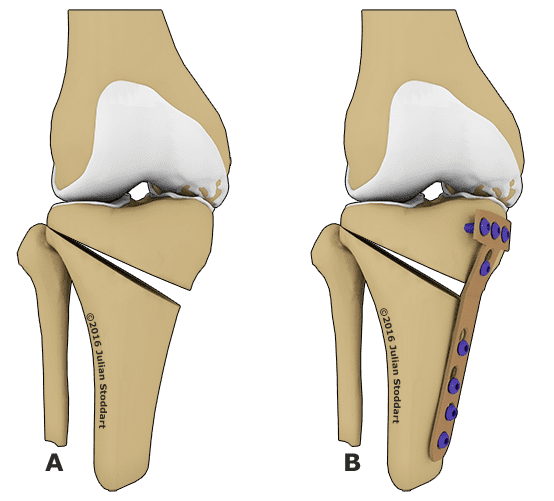

Если традиционная терапия не дает положительного эффекта или заболевание уже запущено, то без хирургической операции не обойтись. Существует несколько видов вмешательств:

- околосуставная остеомия. Эта операция считается очень сложной, поэтому проводится в редких случаях. Она предусматривает подпиливание костей в некоторых местах и их последующее соединение под необходимым углом. Это дает возможность перераспределить нагрузку. Эффект после операции длится не более 5 лет. Однако она эффективна только на ранних стадиях развития. Кроме того, данное вмешательство требует длительного периода восстановления;